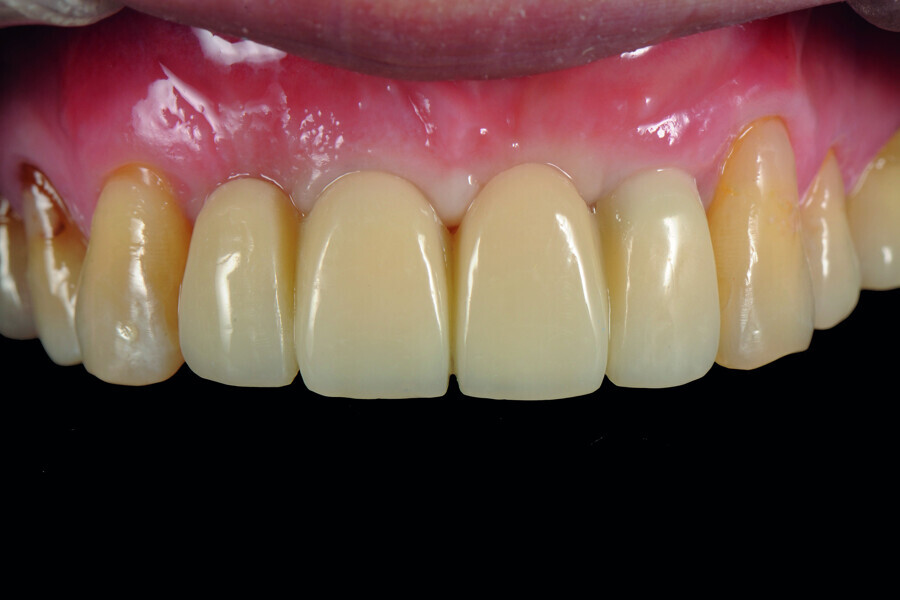

Fig. 43: Frontal view of the anterior teeth just after delivery.